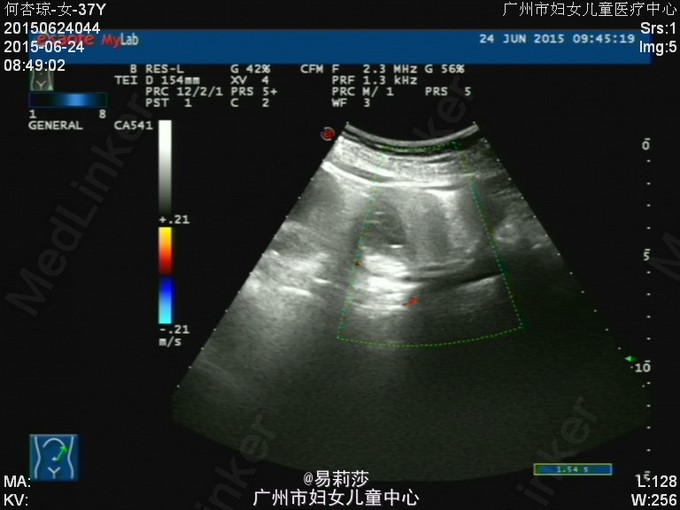

患者何××,女,G0P0,36岁,因“体检发现子宫肌瘤半年”于2015-06-23入院。患者平素月经规则,LMP:2015-06-12。患者于半年前体检时发现子宫肌瘤,未治疗。2月前,患者自觉腹部包块逐渐增大,2015-05-12彩超检查示:子宫前位,后壁见一实性低回声团,范围约125×193×192mm,边界尚清,明显外突,内回声欠均匀,宫腔线隐约可见,双侧附件因肿块遮挡,显示不清,CDFI:上述低回声团内见短棒及条索状血流信号,查血常规示:血红蛋白31g/L,拟“子宫平滑肌瘤”收入我科。入院后查贫血组合示缺铁,予输红细胞悬液6个单位,复查血色素81g/L,患者要求出院,此次再次入院要求手术治疗。查体:T36.2℃,P100次/分,R20次/分,BP132/74mmHg,神清,中度贫血外观,心肺听诊无异常,腹膨隆,宫底达剑突下1cm,无压痛、反跳痛。妇科检查:外阴发育正常,阴毛女性分布;阴道畅,分泌物色白,无异味;宫颈光滑,无肥大,无举痛及着色;宫体前位,增大,宫底达剑突下1cm,质硬,活动差,无压痛;双侧附件未扪及包块及压痛。 辅助检查:2015-06-24彩超检查示:胆囊息肉(胆固醇结晶),副脾,肝、胰、右肾未见明显异常回声,左肾下极异常回声团——畸胎瘤?,考虑来源左侧卵巢可能,与左肾关系密切,巨大子宫肌瘤,左侧卵巢显示不清,请进一步检查。MRI检查示:1.子宫左侧壁巨大实性肿块影,考虑巨大子宫肌瘤可能性大,子宫明显受压;2、左肾下方类圆形病变,考虑畸胎瘤可能性大;3、双侧腹膜后区主动脉、下腔动脉周围见不规则囊状影,考虑淋巴管扩张可能;4、盆腔少量积液。